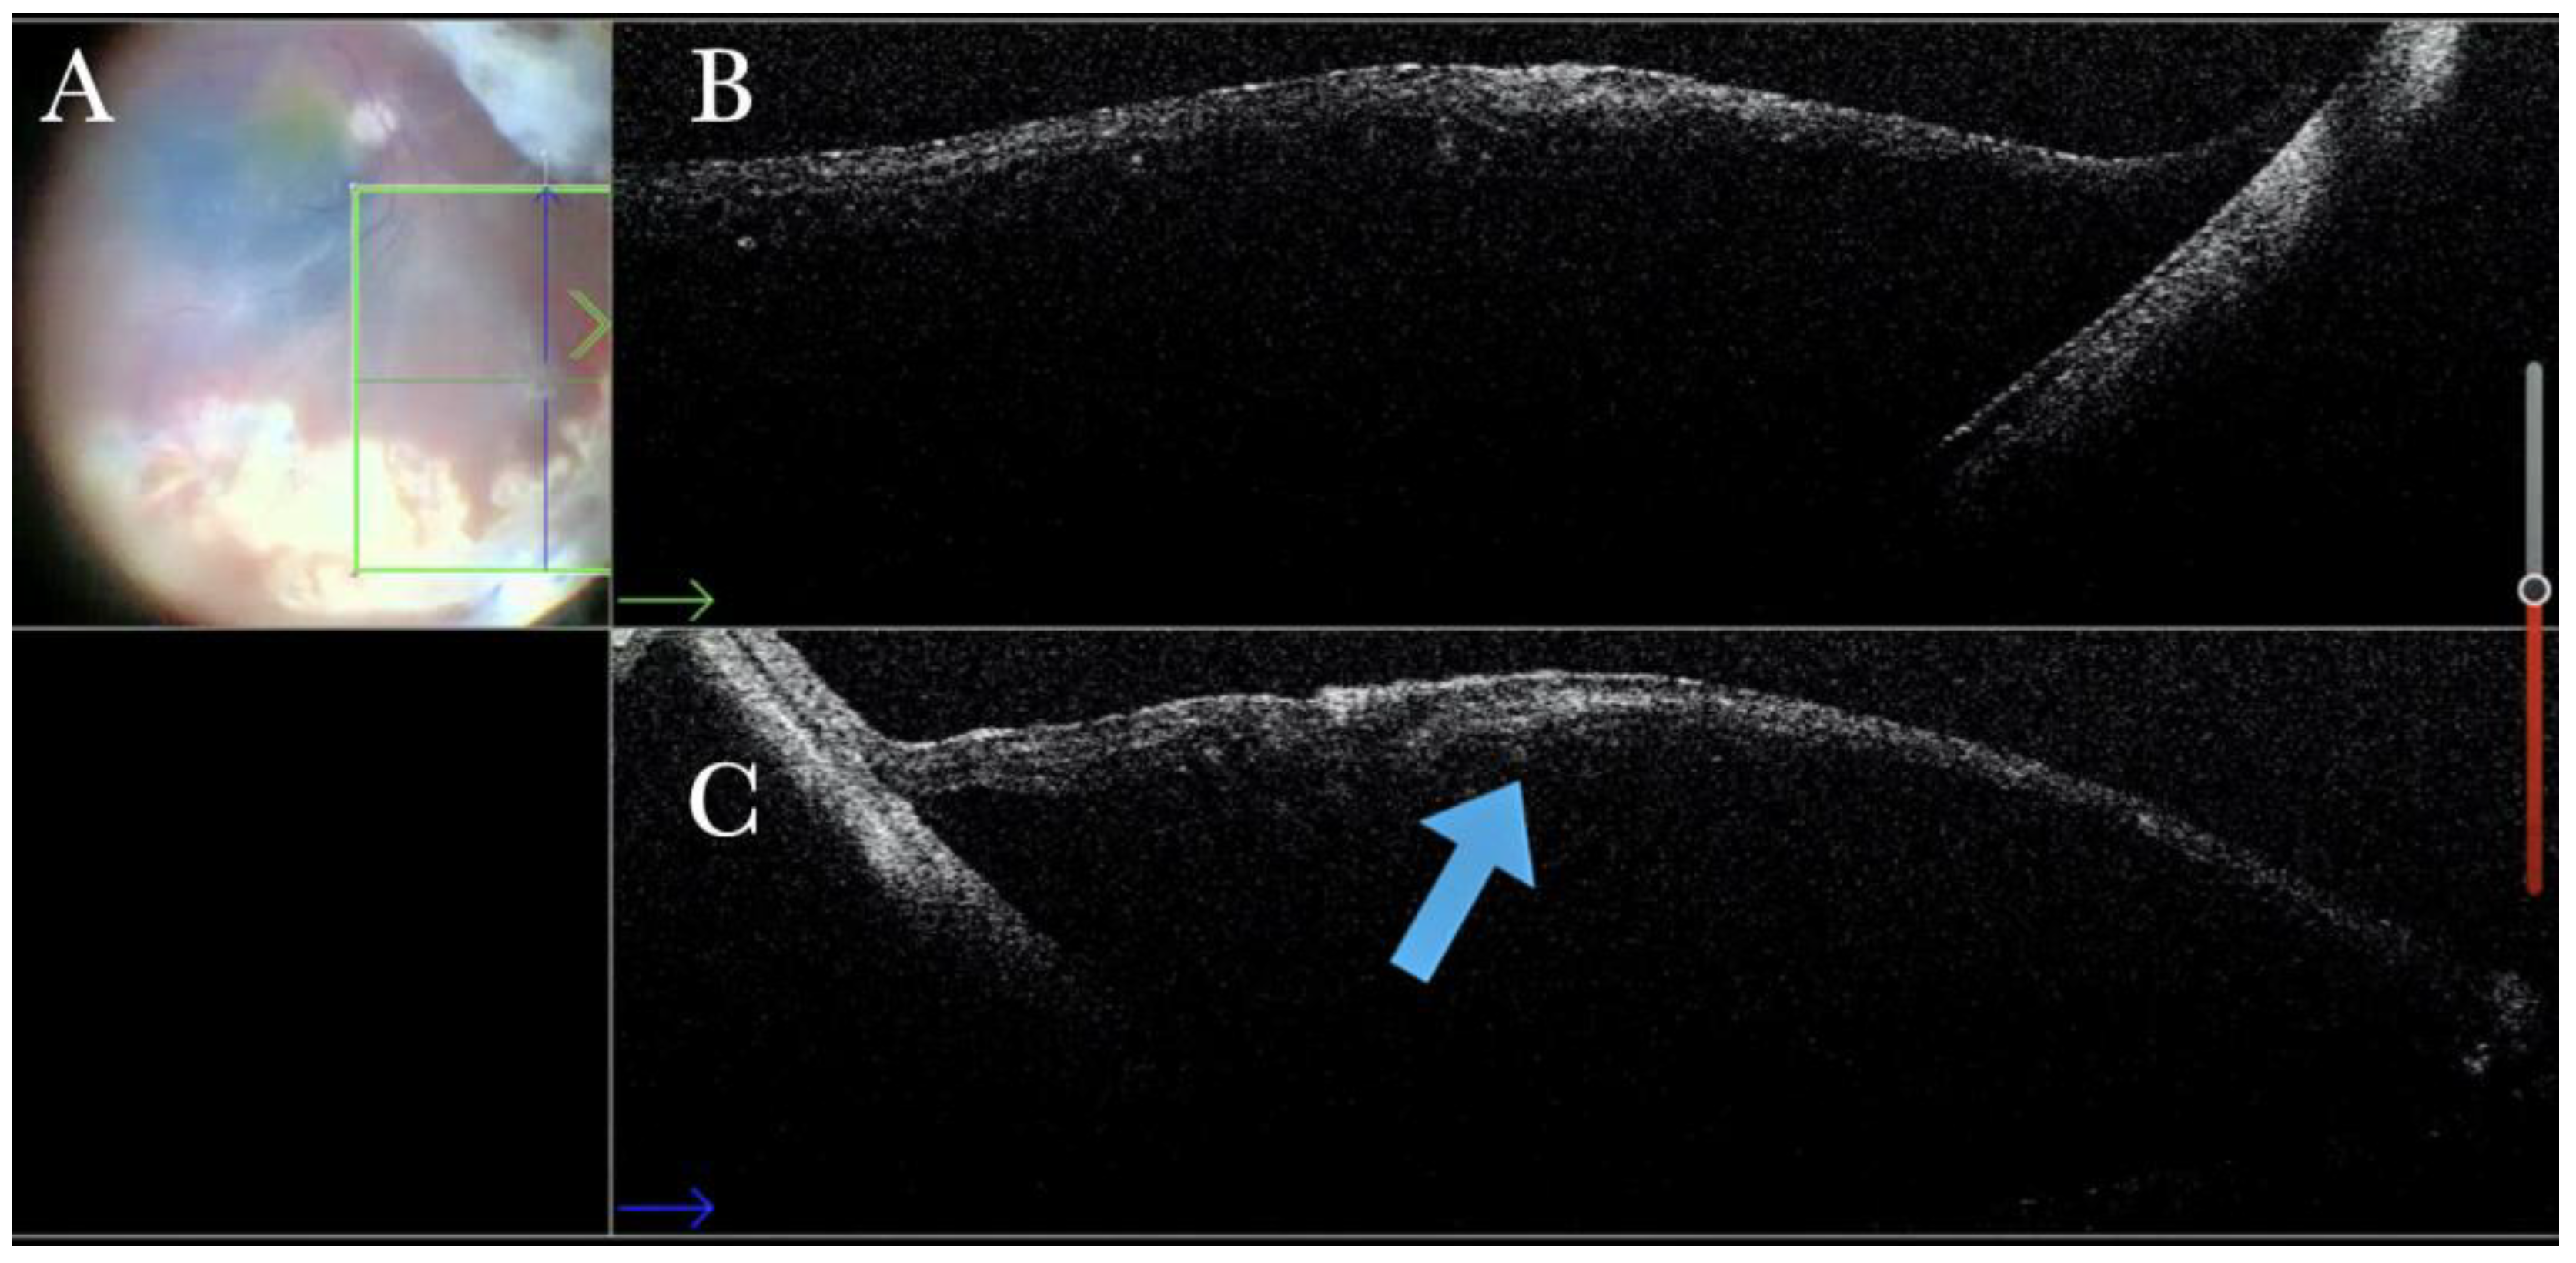

Figure 22.

(A) Microscope view of the macular area in a case of autologous choroidal transplant. The surgeon is inducing a retinal detachment by injecting a balanced salt solution (BSS) through a 41-gauge needle into the macular area. (The green box indicates the field-of-view of the OCT scan, the green and blue lines within the green box show the vertical and horizontal scan planes). (B) The intraoperative optical coherence tomography (i-OCT) horizontal (green arrow) scan shows the detached macula. (C) The i-OCT vertical scan shows the detached macula with a full-thickness macular hole (FTMH) (white arrow) induced during the injection of BSS. The FTMH was not visible through the microscope and could be managed during surgery.

Figure 23.

(A) Microscope view of the temporal retina that is detached and inverted onto the nasal side. A full-thickness patch of the choroid is visible over the macular area and covered by perfluorocarbon liquid (PFCL). (The green box indicates the field-of-view of the OCT scan, the green and blue lines within the green box show the vertical and horizontal scan planes). (B) The intraoperative optical coherence tomography (i-OCT) horizontal (green arrow) scan shows a choroidal patch with no retina on top and covered by PFCL, which is invisible with i-OCT. (C) The i-OCT vertical scan shows a choroidal patch with no retina on top and covered by PFCL, which is invisible with i-OCT.